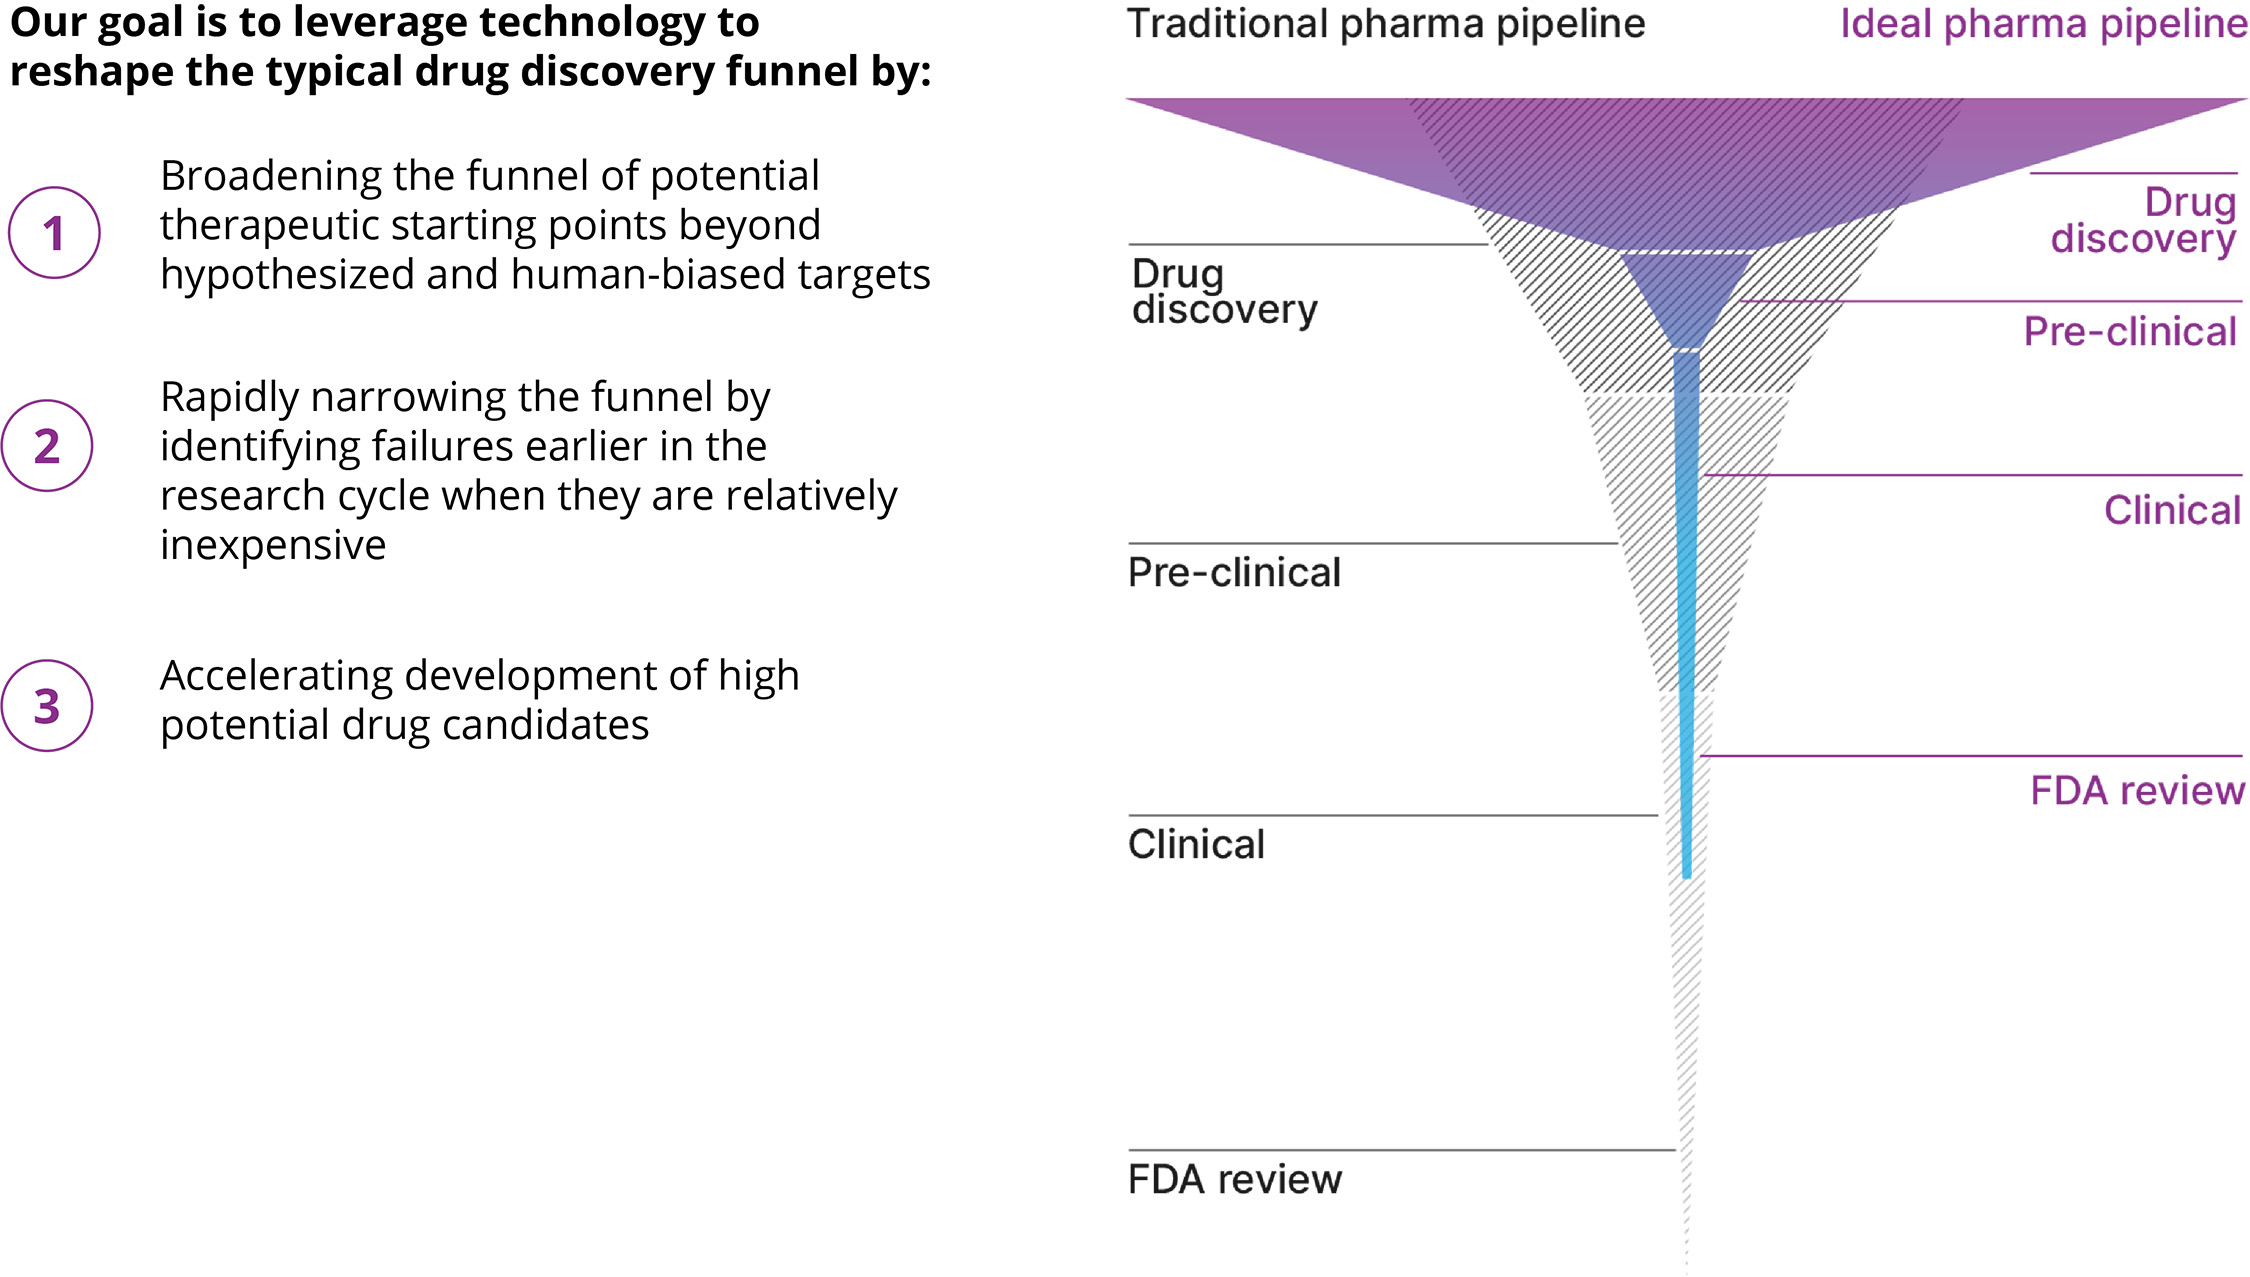

Figure 1. A simple formula is used across technology industries to map and navigate complex systems. First, high-dimensional data is generated, aggregated and organized to create digital representations. Then, AI/ML algorithms make predictions about that system that can be tested in reality. The result is a virtuous cycle of learning and iteration.

How Recursion is Industrializing the Drug Discovery Process

The traditional drug discovery and development process is characterized by substantial financial risks, with increasing and long-term capital outlays for development programs that often fail to reach patients as marketed products. Historically, it has taken over ten years and an average capitalized R&D cost of approximately $2 billion per approved medicine to move a drug discovery project from early discovery to an approved therapeutic. Such productivity outcomes have culminated in a rapidly declining internal rate of return for the biopharma industry.

Figure 5. Historical biopharma industry R&D metrics. The primary driver of the cost to discover and develop a new medicine is clinical failure. Less than 4% of drug discovery programs that are initiated result in an approved therapeutic, resulting in a risk-adjusted cost of approximately $1.8 to $2.6 billion per new drug launched.3,4,5,6,7

Despite significant investment and brilliant scientists, these metrics point to the need to evolve a more efficient drug discovery process and explore new tools. Traditional drug discovery relies on basic research discoveries from the scientific community to elucidate disease-relevant pathways and targets to interrogate. Coupled with biology’s incredible complexity, this approach has forced the industry to rely on reductionist hypotheses of the critical drivers of complex diseases, which can create a ‘herd mentality’ as multiple parties chase a limited number of therapeutic targets. The situation has been exacerbated by human bias (e.g., confirmation bias and sunk-cost fallacy). Accentuating this problem, the sequential nature of current drug discovery activities and the challenges with aggregation and relatability of data across projects, teams and departments lead to frequent replication of work and long timelines to discharge the scientific risk of such hypotheses. Despite decades of accumulated knowledge, the result is that drug discovery has unintentionally created hurdles for innovation.

Simultaneously, exponential improvements in computational speed and reductions in data storage costs driven by the technology industry, coupled with the rapid rise of large language models, generative AI and other ML tools, have transformed complex industries from media to transportation to e-commerce. Historically, the biopharma sector has been slow to embrace such innovations. Within the past 18 months, there have been remarkable shifts in perception among technology and biopharma companies as well as among regulators and policymakers, who highlight the utility of AI/ML for broad drug discovery and development from novel target discovery through next-generation manufacturing. We believe this rapid acceleration and adoption of these technologies demonstrates the growing consensus that AI/ML is a catalyst for substantial leaps in drug discovery.

At Recursion, we are pioneering the integration of innovations across biology, chemistry, automation, data science and engineering to industrialize drug discovery in a full-stack solution across dozens of key workflows and processes critical in discovering and developing a drug. For example, by combining advances in high content microscopy with arrayed CRISPR genome editing techniques, we can rigorously profile massive, high-dimensional biological and chemical perturbation libraries in multiple human cellular contexts to create digital ‘maps’ of human biology. Leveraging advances in scaled computation, we can conduct massive virtual screens to predict the protein targets for billions of chemical compounds. Similarly, data generated from our automated DMPK module and InVivomics platform enables us to predict ADME properties and identify toxicity signals, respectively, significantly faster than traditional methods. We believe that by harnessing advances in technology to industrialize drug discovery, we can derive novel biological insights not previously described by scientific researchers, reduce the effects of human bias inherent in discovery biology and reduce translational risk at the program outset.

Figure 6. Recursion’s approach to drug discovery. We utilize our Founding Principles on the right to build datasets which are scalable, reliable and relatable in order to elucidate novel biological and chemical insights and industrialize the drug discovery process.